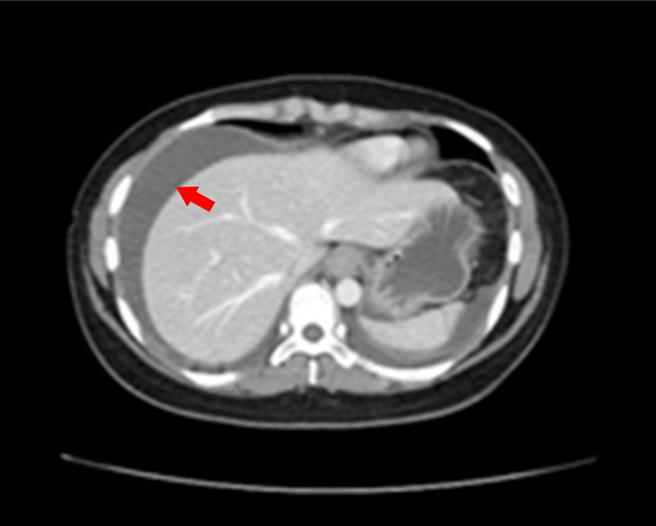

李政祺表示,这位女性患者在急诊时抽血验出她的白血球数高达23000(正常为400至10000),其中嗜酸性白血球比例29%(正常为5%),腹部电脑断层发现小肠壁变厚且有明显腹水情形,经收治住院治疗。

1位30岁女性因腹胀、腹痛、呕吐、腹泻挂急诊,经断层扫描检查发现患者有明显腹水。(澄清院提供/冯惠宜台中报导)